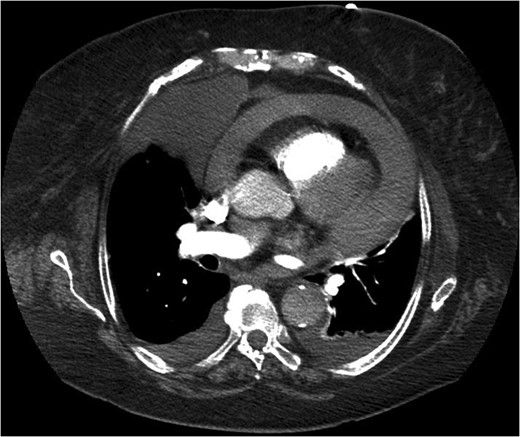

An 83-year-old woman presented to accident and emergency with sudden symptoms of abdominal pain and vomiting. She had presented a month earlier with similar symptoms and dysphagia, which had been ongoing for 2 weeks. Clinical examination had shown reduced air entry in the right lung and a normal abdomen. Chest X-ray showed consolidation in the lower right zone but with no symptoms or signs of a lower respiratory tract infection. She was taken under the care of the medical team and went on to have a computed tomography (CT) scan (Fig. 1) of her chest, which revealed a Bochdalek's hernia. Her symptoms settled, and she was discharged without a surgical review.

She represented later to our unit with recurrent vomiting. Her investigations revealed a raised lactate and acidosis on arterial blood gas. There was a concern for gastric ischaemia; the decision was taken to proceed to theatre. Given that she was haemodynamically stable with no peritonitis, we chose to operate using a laparoscopic approach. Surgery was performed through four laparoscopy (2 × 11 mm, 2 × 5 mm). A diagnosis of Morgagni hernia was made (Fig. 2). Inside the hernial sac was the transverse colon, the greater curvature of the stomach with a partial gastric volvulus (Fig. 3). The hernia was reduced with the viscera still viable but the sac could not be excised. The defect was repaired with a 6 × 10 cm composite mesh with an absorbable tic fixation on the diaphragm (Fig. 4). No drain was inserted, and the operation time in total was 45 minutes.